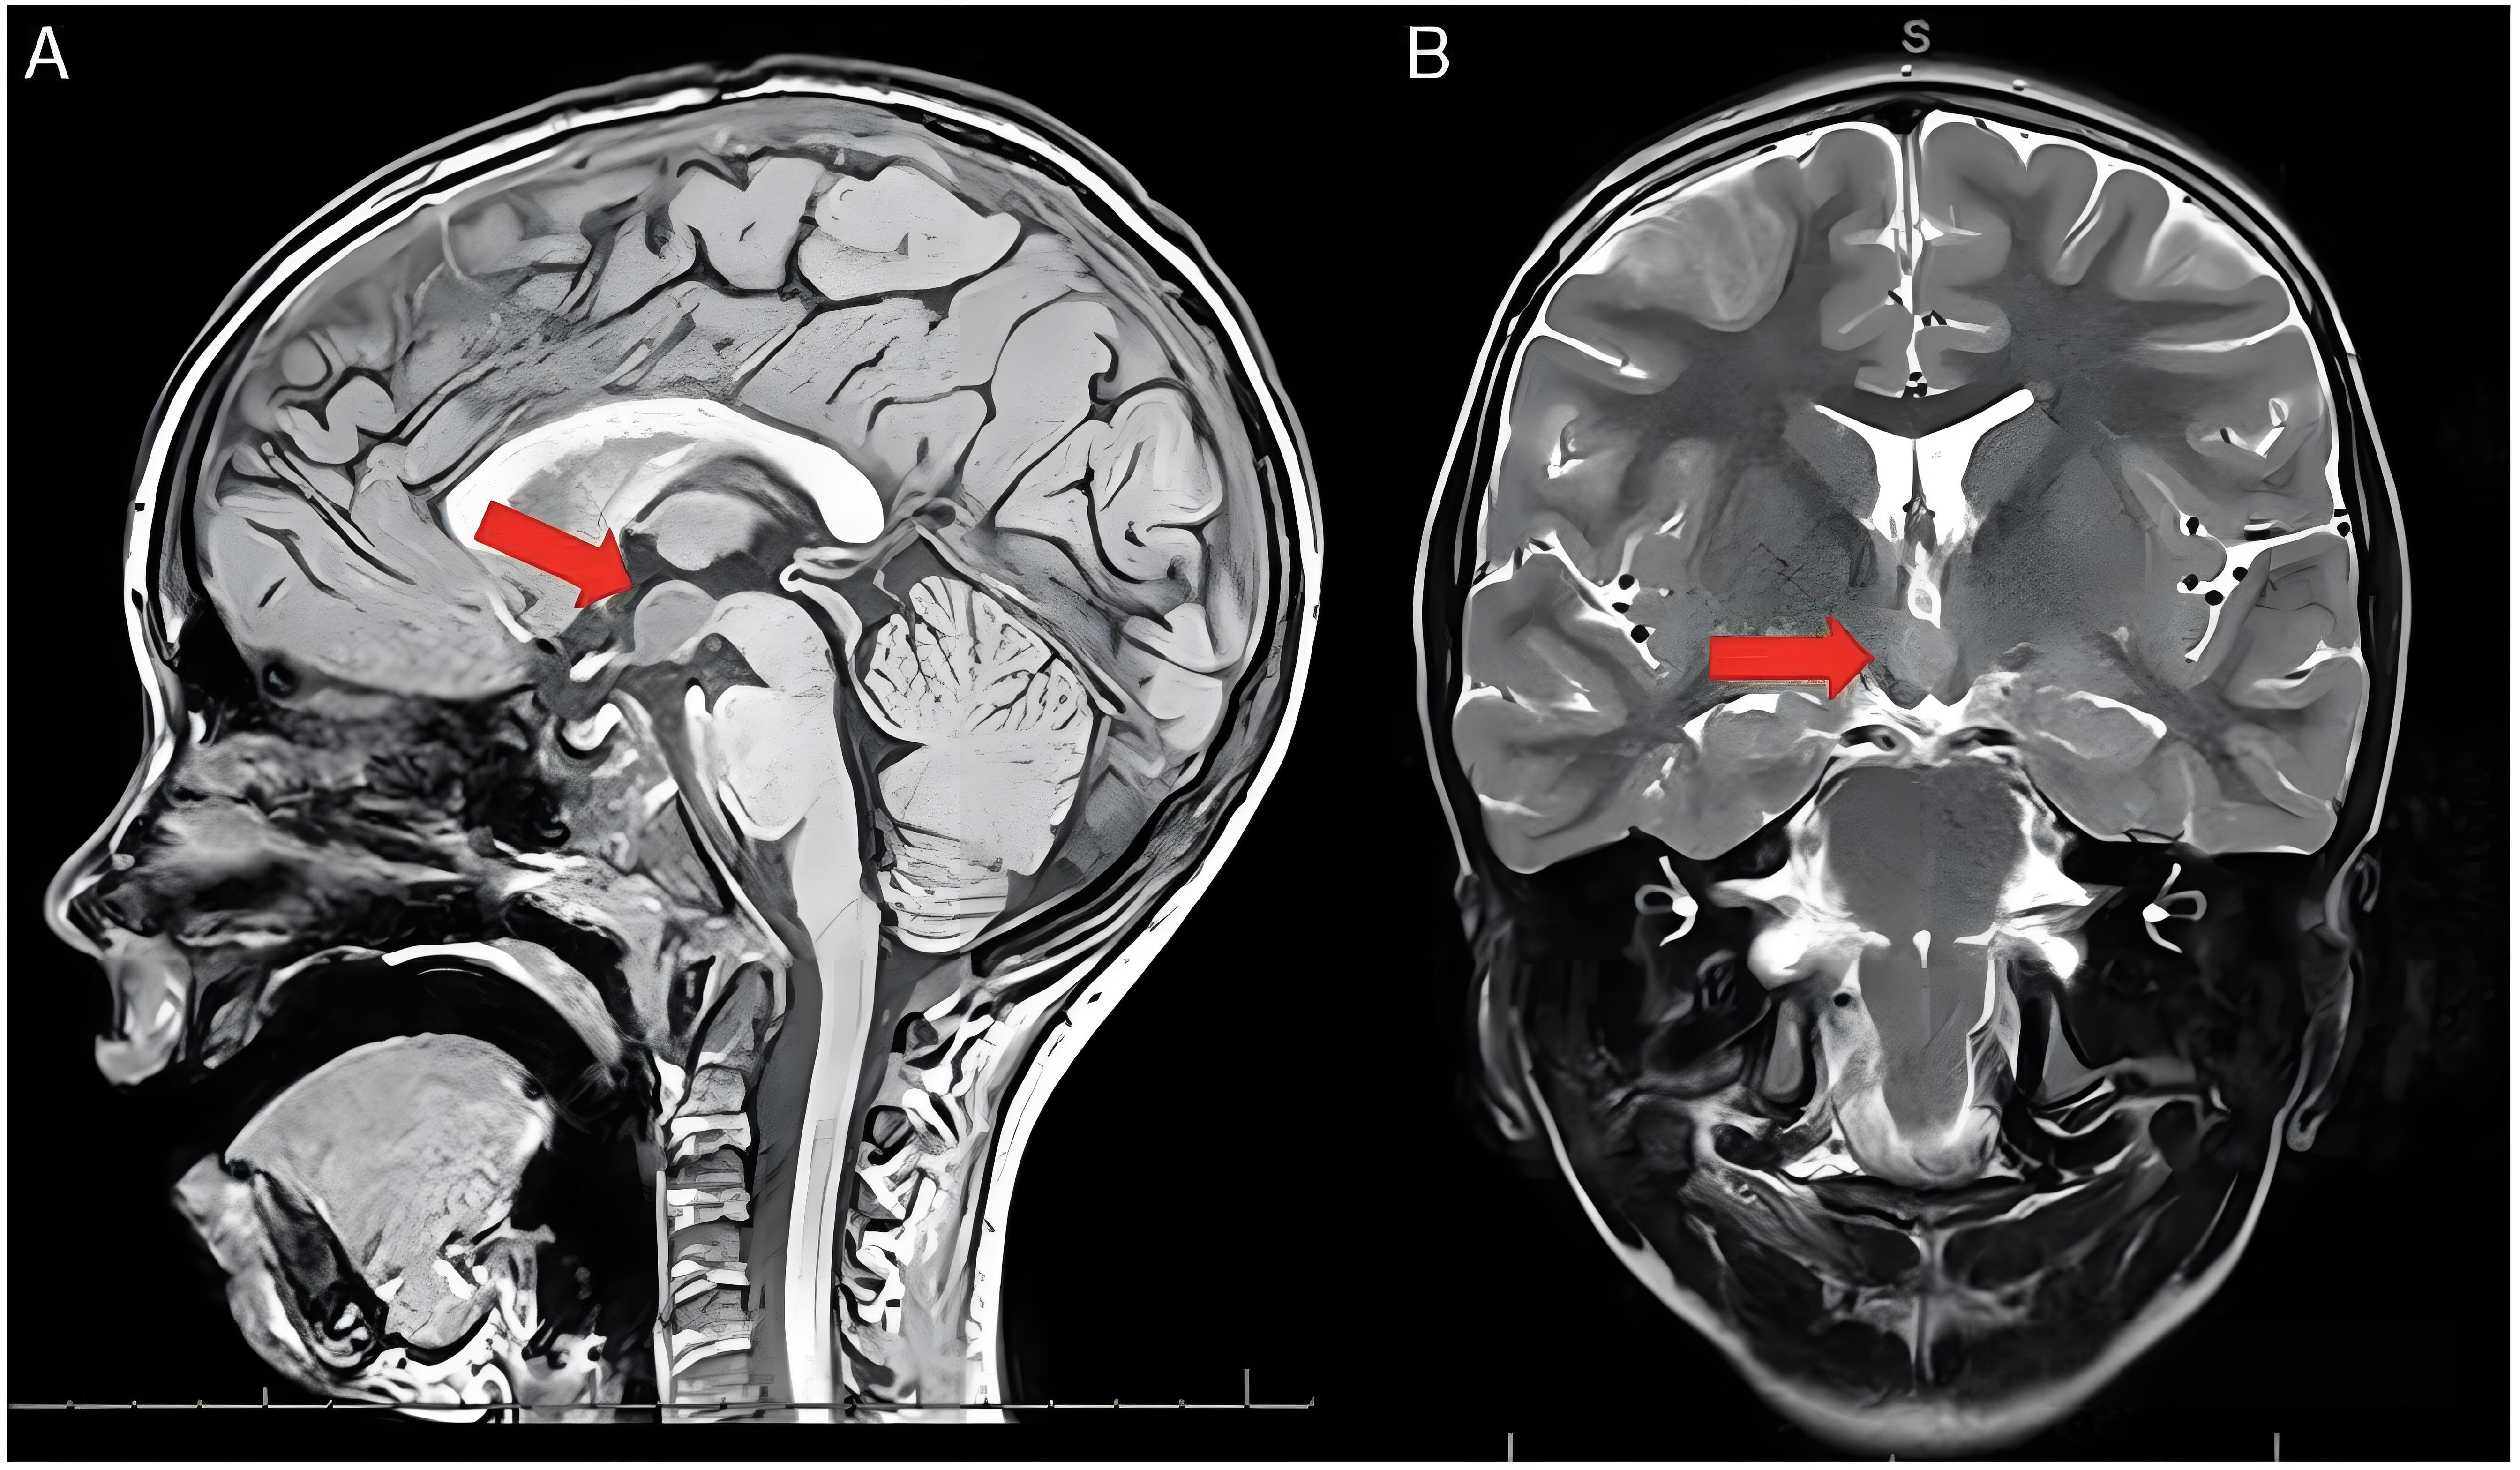

头颅MRI:排查下丘脑病变

医生手记:曾遇7岁女孩初诊为单纯发育,因骨龄超前做MRI,最终发现下丘脑错构瘤——早诊断避免了癫痫发作。